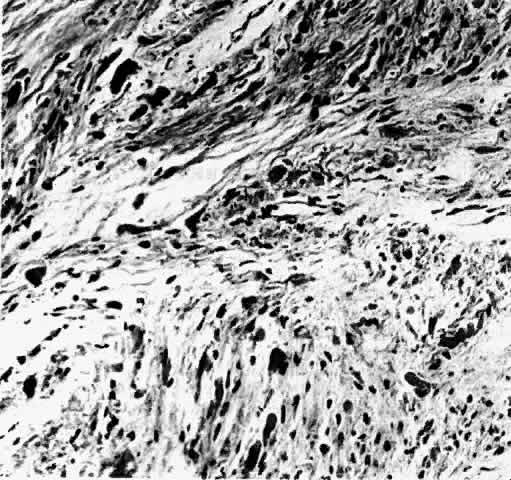

Controversy exists as to whether optic gliomas are hamartomas or true neoplasms. The tumors were first described as hamartomas by Hudson in91 In 1969, Hoyt and Baghdassarian92 supported Hudson's theory and concluded that optic gliomas represented congenital, non-neoplastic tumors with self-limited growth followed by stability. Histologic features and growth rates, however, suggest that optic gliomas are true neoplasms. Burnstine93 evaluated optic gliomas with colloid silver impregnation of nucleolar organizer region-associated proteins (AgNORs) whose size, number, and morphology indicate the pattern of cell proliferation or transformation. Optic glioma AgNOR counts were similar to optic nerve meningiomas and had features consistent with true neoplasms (Fig. 10). In a review of 623 reported cases, Alvord and Lofton2 described optic nerve growth kinetics based on time to recurrence of disease. Growth patterns had variable rates, ranging along a continuum from a simple logarithmic rate to a decelerating growth rate; these rates were not characteristic of hamartomas.

Fig. 10. Colloid silver impregnation of optic nerve glioma demonstrating muliple nucleolar organizer region-associated proteins (AgNORs) in each nucleus. (Burnstine MA, Levin LA, Louis DN et al: Nucleolar organizer regions in optic gliomas. Brain 116:1564, 1993. Reproduced with permission from Oxford University Press.)